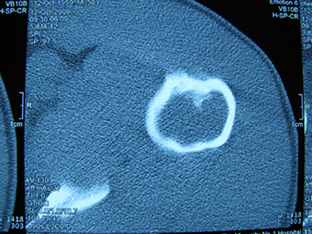

标题: X6404B:肱骨骨质破坏(CT片) [打印本页]

标题: X6404B:肱骨骨质破坏(CT片)

男,50岁,左肩部轻微疼痛,活动不便5个月就诊,近十天加重,无红肿热,间断理疗治疗无好转,既往5个月前左肩轻微拉伤史

骨巨?动脉瘤样骨囊肿?

内生软骨瘤。

内生软骨瘤。

内生软骨瘤?-----------

年纪大了,先要排除转移瘤。

髓腔内软组织肿块并斑片状钙化,考虑高分化软骨肉瘤可能性大。

考虑骨巨或动脉瘤样骨囊肿。

内生软骨瘤可能性大,期待结果。

孤立性骨囊肿。

内生软骨瘤可能性大

其内可见钙化,考虑软骨源性肿瘤,内生软骨瘤可能

但由于年龄较大,恶性软骨肉瘤待排

肱骨头内巨大软组织肿块并斑片状钙化,内生软骨瘤?骨巨细胞瘤?软骨粘液样纤维瘤?期待结果!

髓腔内软组织肿块并斑片状钙化,考虑高分化软骨肉瘤可能性大。

内生软骨瘤可能性大

肱骨头内巨大软组织肿块并斑片状钙化,内生软骨瘤?骨巨细胞瘤?软骨粘液样纤维瘤?期待结果

考虑内生软骨瘤?骨巨细胞瘤?

内生软骨瘤?骨巨细胞瘤?

先要排除转移瘤。